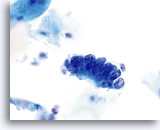

Adenocarcinoma in situ

Variably sized, crowded, hyperchromatic groups of cells are seen on screening power which warrant a closer inspection. 20x